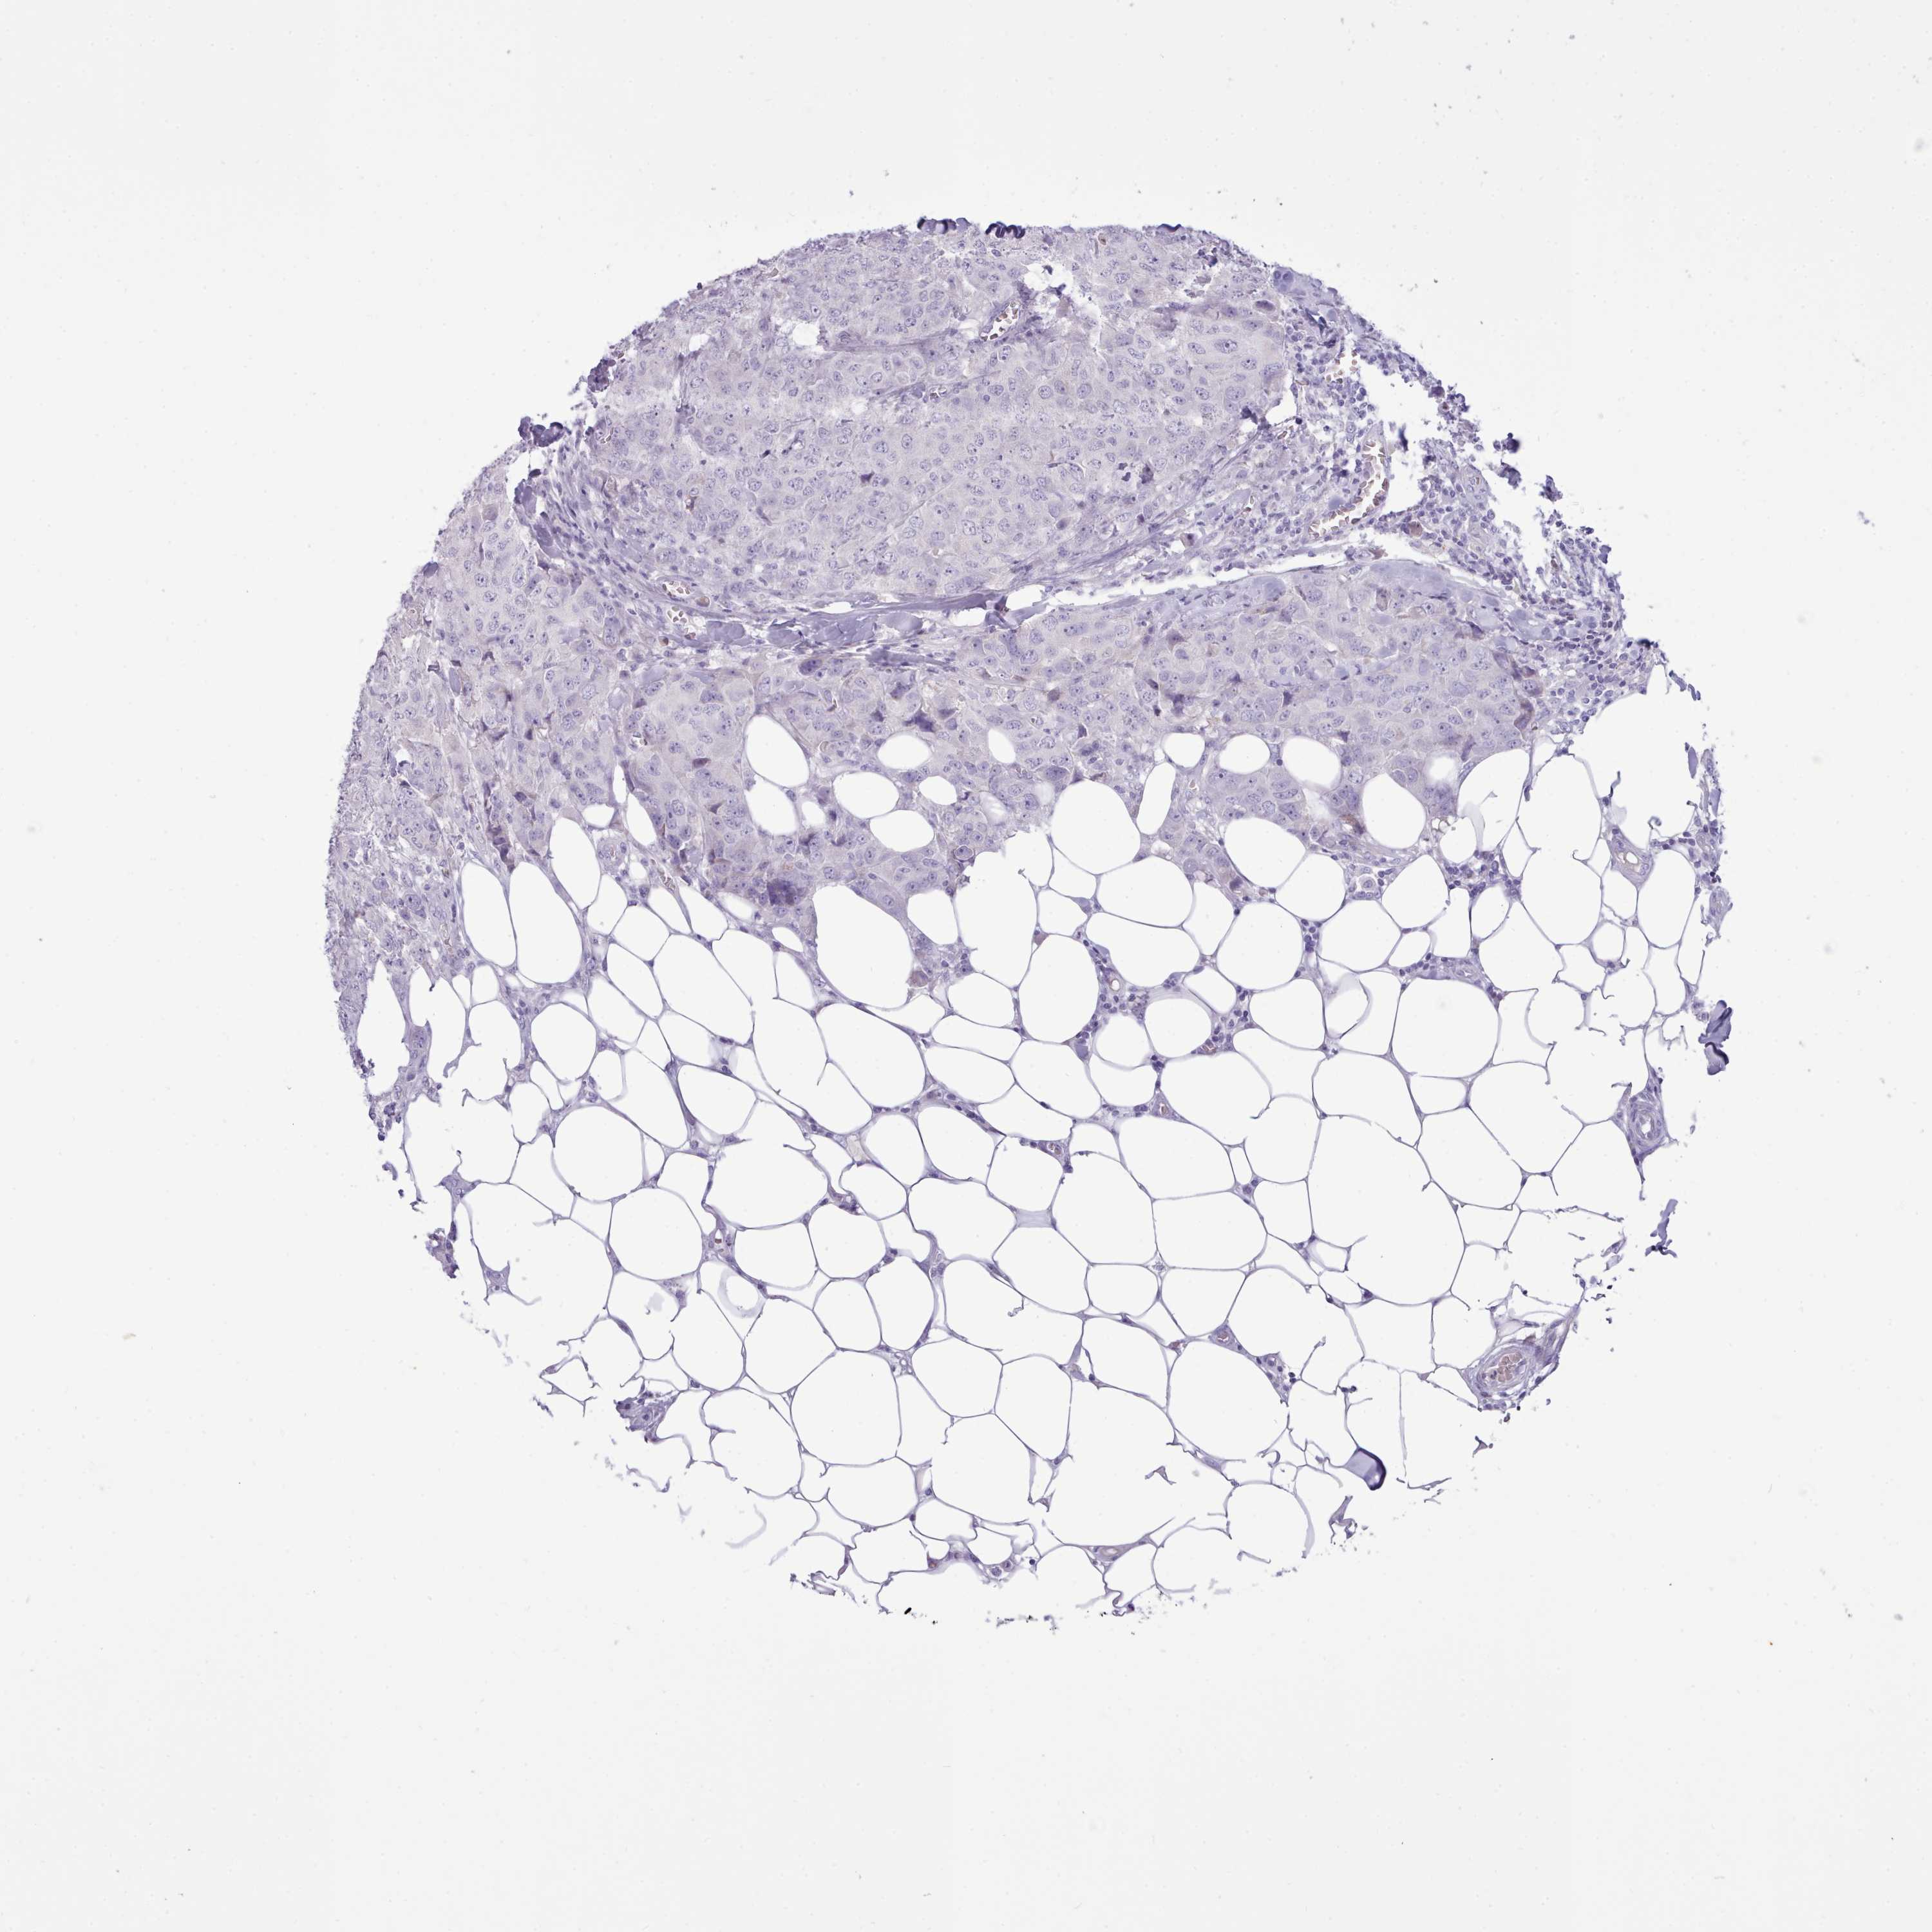

BRCA TCGA BRCA VALIDATION PROTEIN EXPRESSION

ANTIBODIES

AND

VALIDATION